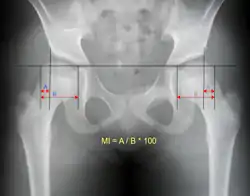

Anterior-posterior (AP) X-rays of the pelvis, AP and lateral views of the femur (knee included) are ordered for diagnosis.[13] The size of the head of the femur is then compared across both sides of the pelvis. The affected femoral head will appear larger if the dislocation is anterior, and smaller if posterior.[14] A CT scan may also be ordered to clarify the fracture pattern.